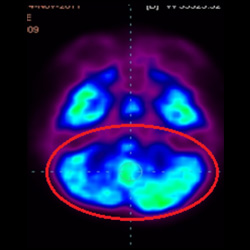

細(xì)胞治療后,藍(lán)色和黑色區(qū)域減少,并且看到更活躍的區(qū)域。這表明損傷減少并改善了大腦功能。

細(xì)胞治療前 PET CT 掃描顯示神經(jīng)組織中的藍(lán)/黑色區(qū)域,表明腦癱引起的大腦損傷。

這證明細(xì)胞療法是治療腦癱兒童安全有效的方法。細(xì)胞療法可以更新大腦損傷的核心,并且可以通過 PET CT 掃描來監(jiān)測大腦的改善情況。這些細(xì)胞療法與標(biāo)準(zhǔn)治療一起促進(jìn)腦癱兒童的生長和改善。